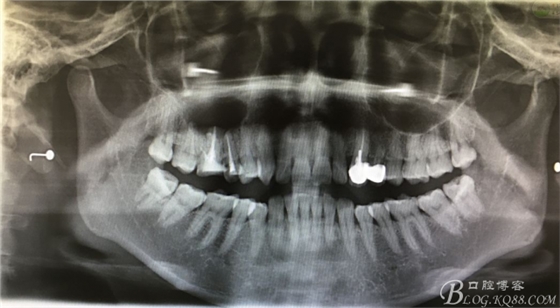

圖4.全景片影像檢查:以16為中心的橢圓形陰影,當時15未作根管治療。